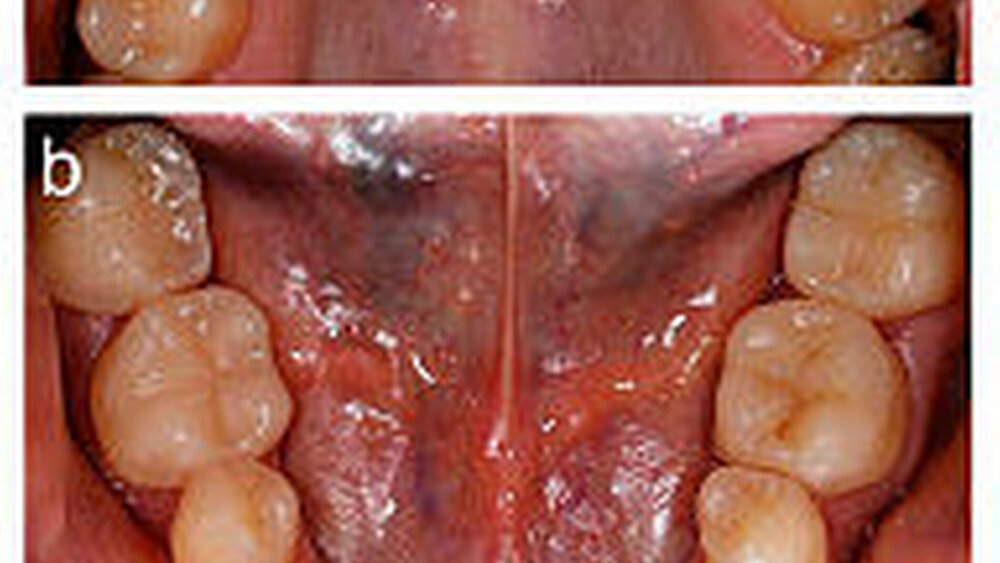

Eine 31 Jahre alte Patientin war von einem zahnärztlichen Kollegen zur weiteren Therapie überwiesen worden. Wie in Abbildung 1 zu erkennen, wies sie an allen Zähnen erosive Defekte auf, die sich bevorzugt auf den Okklusal- und Palatinalflächen im Seitenzahngebiet manifestiert hatten. Im Frontzahngebiet lagen sowohl palatinal als auch inzisal-bukkal erosiv veränderte Zahnoberflächen vor. Die Patientin gab an, unter gastroösophagealem Reflux zu leiden, der medikamentös mit H2-Blockern von ihrem Hausarzt behandelt und kontrolliert wurde. Sie litt unter Hypersensibilitäten der Seitenzähne. Zudem störte sie das Erscheinungsbild ihrer Oberkieferfrontzähne.